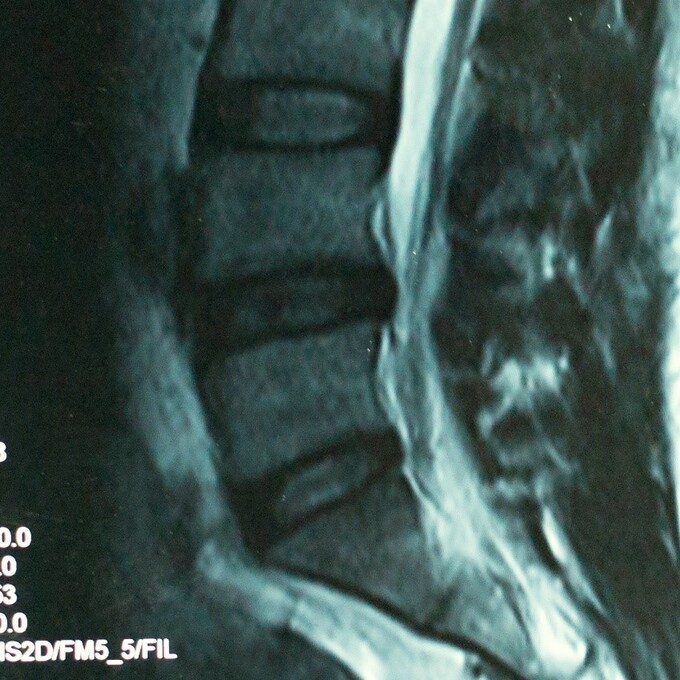

Có nhiều cách được sử dụng kết hợp để chẩn đoán thoát vị đĩa đệm thắt lưng, đầu tiên qua phim chụp chẩn đoán hình ảnh, phim X quang và cộng hưởng từ MRI nhưng quan trọng là phim cộng hưởng từ. Tiếp theo, bác sĩ cần biết được tiền sử bệnh lý, bệnh nhân có cảm thấy đau từ lưng lan xuống chân không, bởi đau tê lan xuống chân là triệu chứng điển hình của các vấn đề liên quan đến đĩa đệm. Sau đó, khi nhìn vào phim chụp cộng hưởng từ, bác sĩ có thể quan sát tình trạng đĩa đệm có chèn ép vào dây thần kinh hay không.